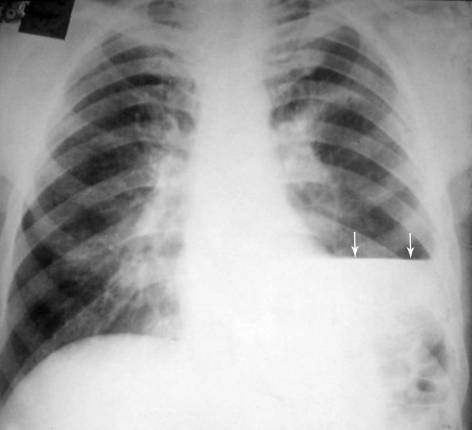

Дифференциальная диагностика заболеваний плевры